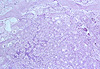

CASO N° 1 (Dr. Jair e Dr. Delgado)

Paciente do gênero masculino, 44 anos de idade, apresenta uma lesão no palato duro e palato mole.